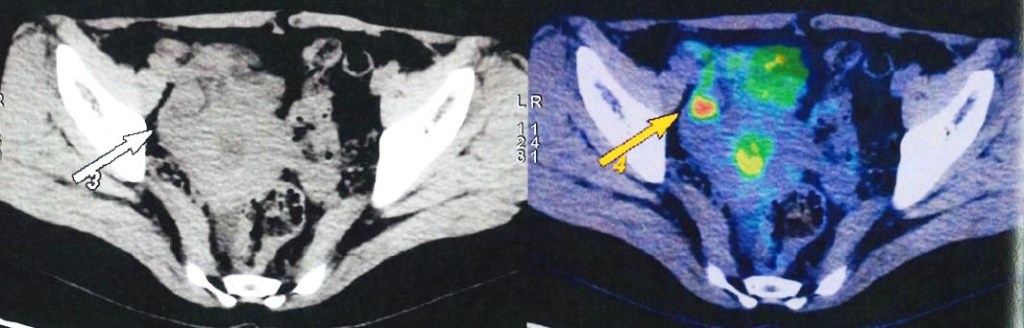

Small hypermetabolic focus in right corn of uterine cavity can be inflammatory change, but malignancy is not excluded. Gynecological evaluation is recommended.

My question to that argument is: With that extra information, what can you do about the real problem? For example, PET scan showed there are nodules in the lungs and a “hot spot” in the uterine cavity. So what did the surgeon do about this “finding or knowledge”? The surgeon did nothing since her/his job is only to cut off the breast! Also, how sure are you that these “extra information” can really save your life?